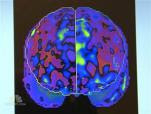

Instead of studying chemotherapy's effect on the brain's appearance, Rachael A Lagos, D.O., and colleagues at the West Virginia Univeristy School of Medicine instead looked at its effect on brain function through an analysis of PET/CT brain imaging results utilizing special software.

What a difference that made. The proof was in the scans where "statistically significant decreases in regional brain metabolism" were noted. Those changes were seen in areas associated with contentration and memory.